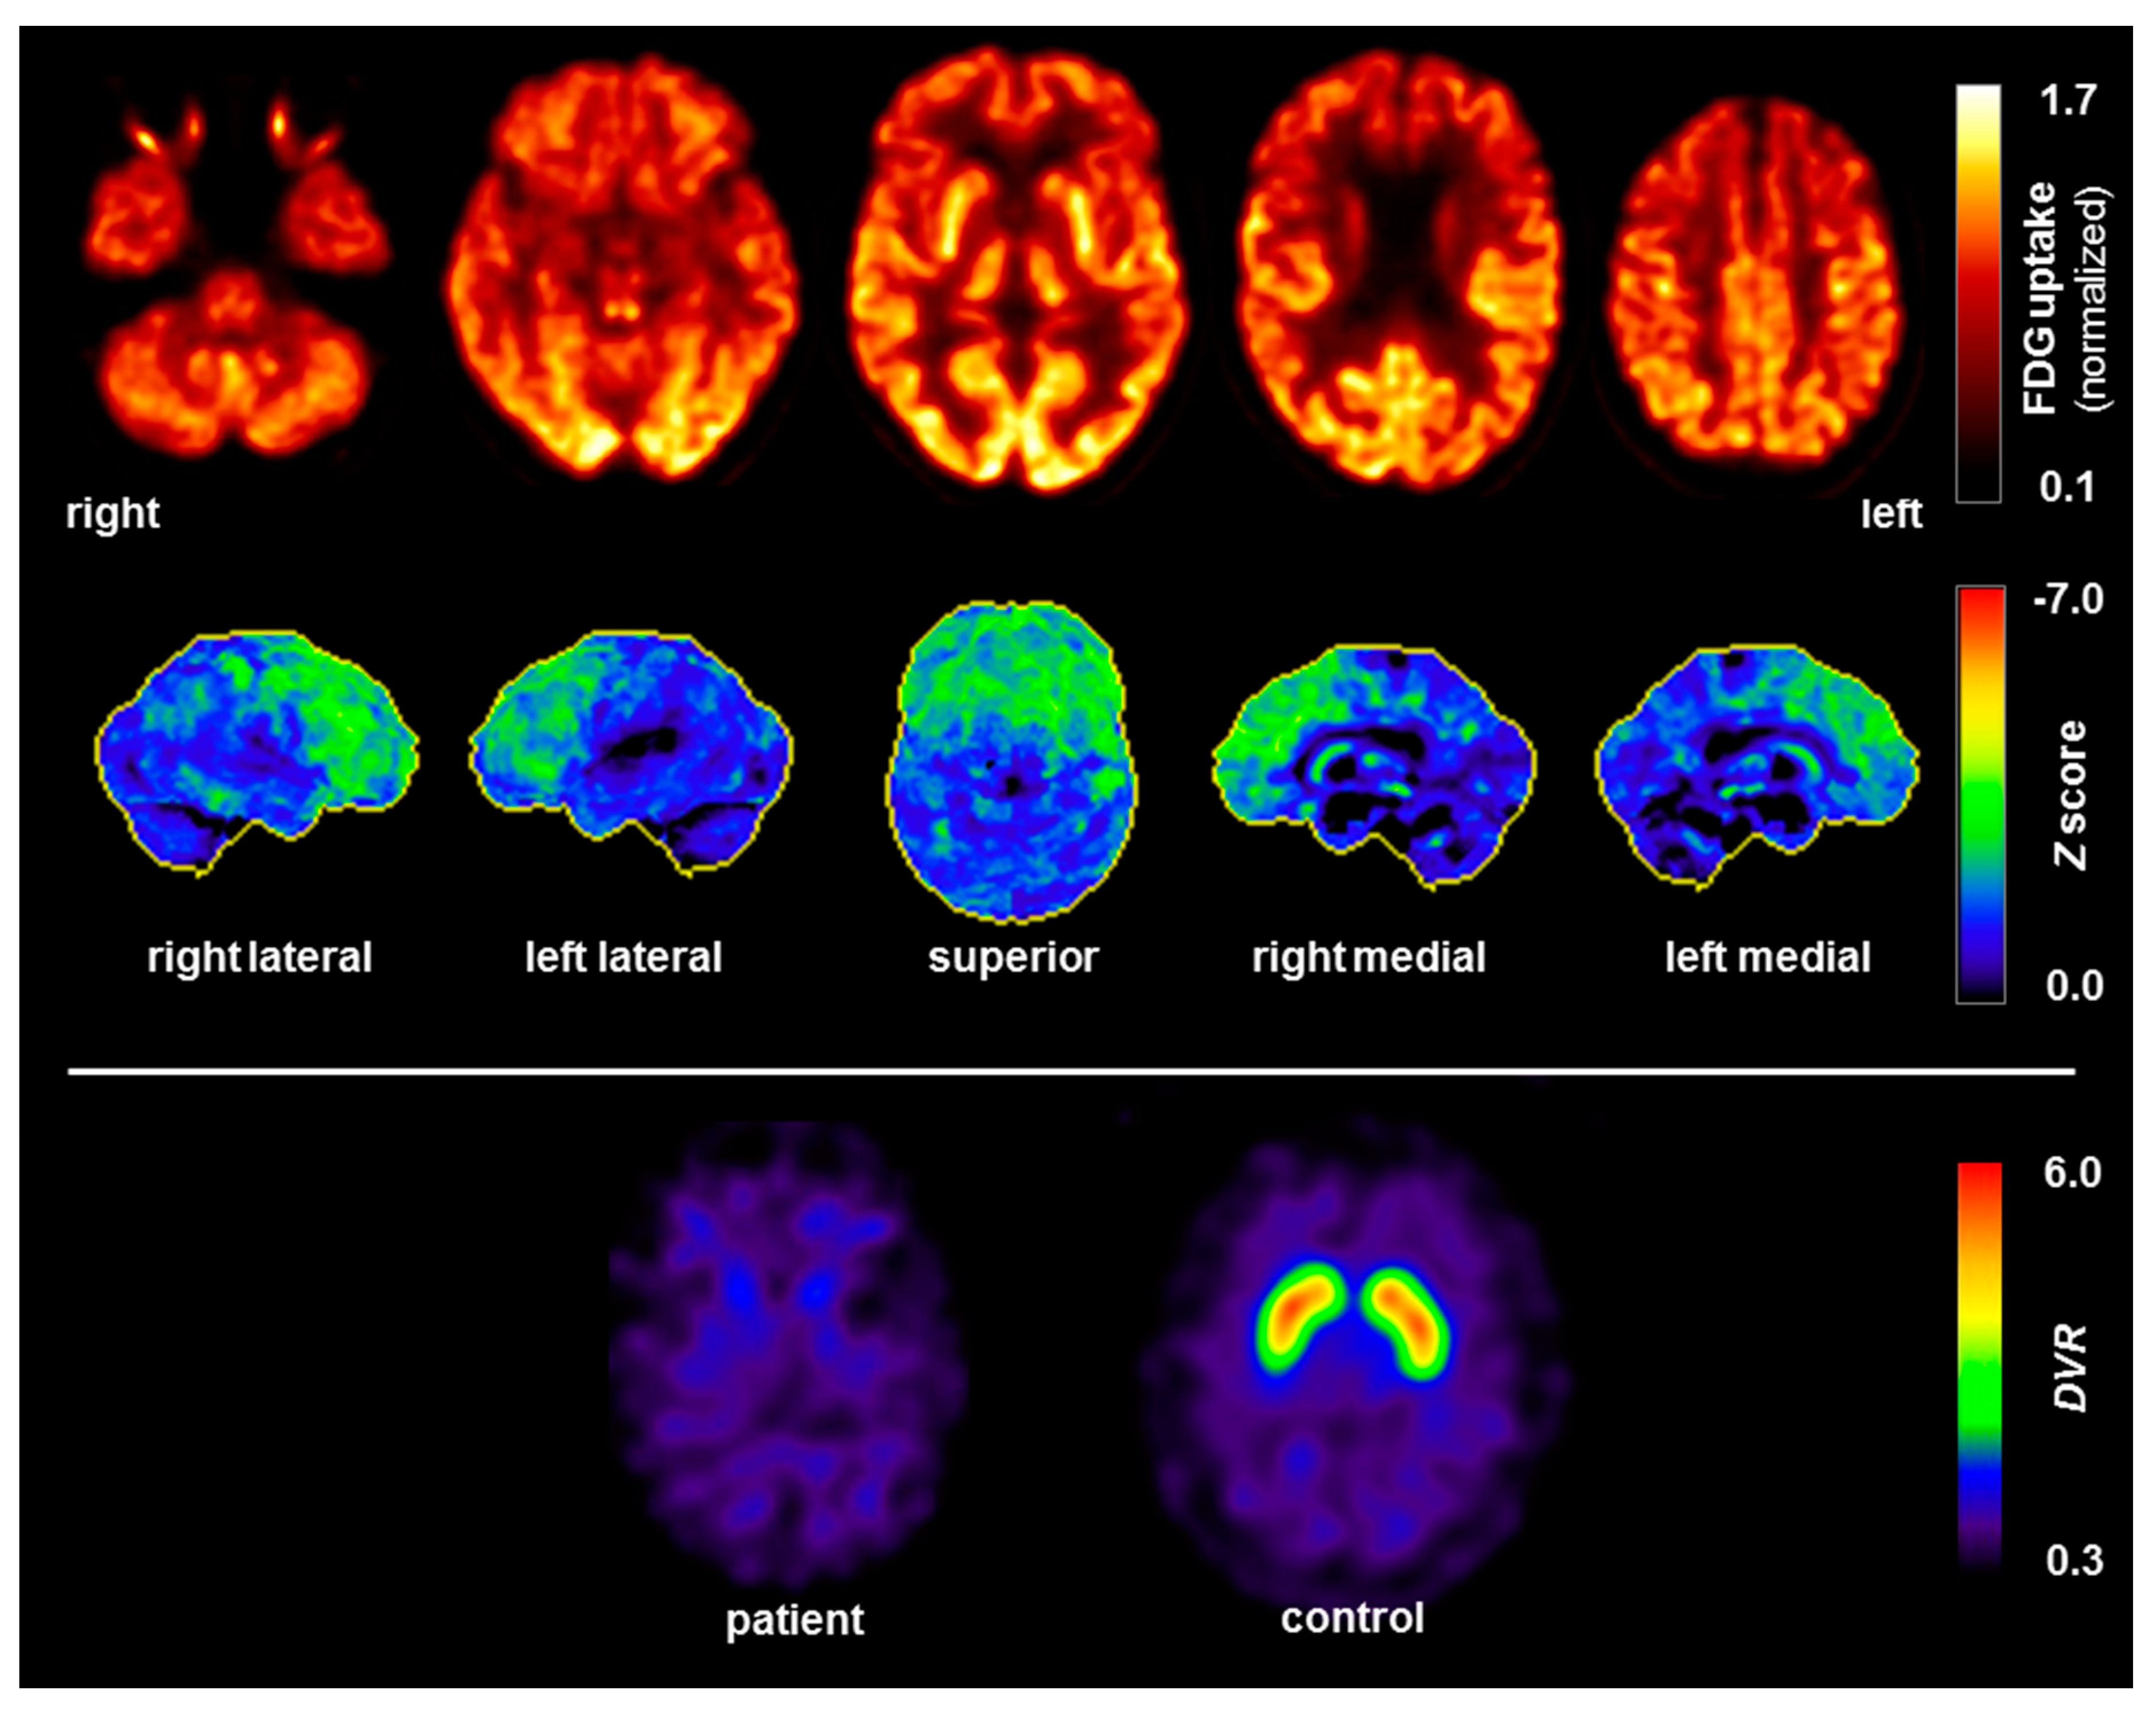

| [18F]fluorodeoxy-glucose positron emission tomography (FDG PET) |

- The anti-GlyR antibodies could have been generated first, thereby triggering a clinical phenotype as a Parkinsonian syndrome with frontal lobe involvement. This is conceivable in principle, but very unlikely in the presented patient; no typical signs of autoimmune anti-GlyR antibody syndrome presently known (e.g., hyperexcitability, anti-GlyR antibodies in CSF, or other inflammatory CSF changes) were detected [17]. Furthermore, the instrument-based diagnostics, using EEG, MRI and FDG PET, as well as the poor response to anti-inflammatory treatment did not support the hypothesis of underlying autoimmune encephalitis.